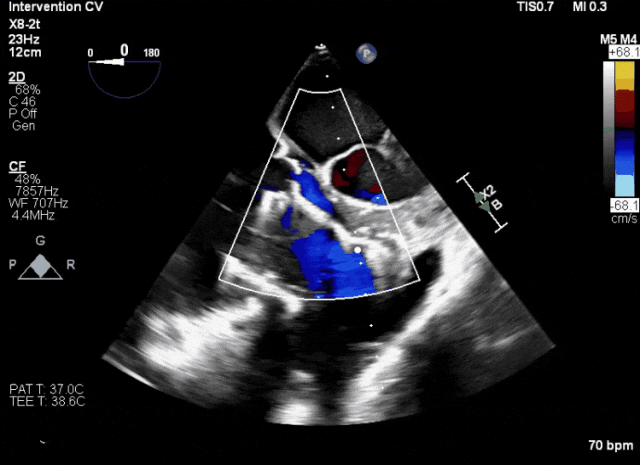

術前超聲顯示三尖瓣重度反流合并拴系

術中TEE成像困難,偽影干擾